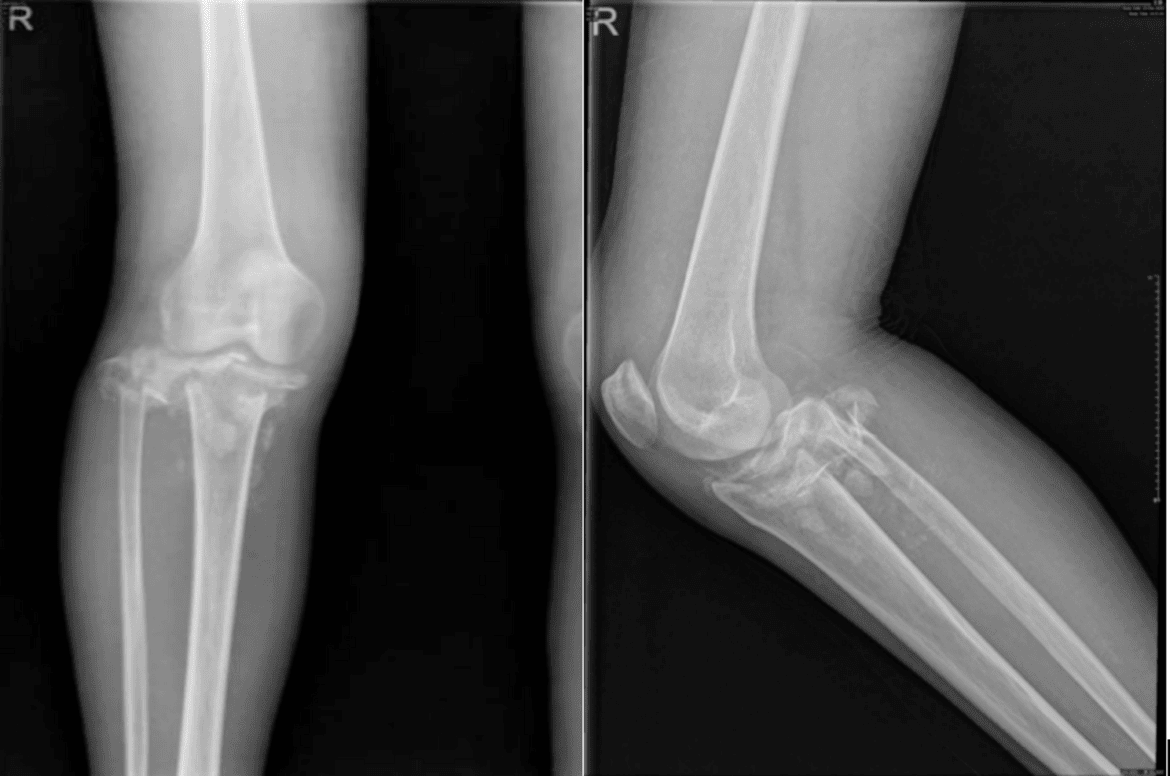

In early-stage disease, non-surgical treatments such as plaster casting or knee bracing, combined with avoidance of weight-bearing, are used to prevent severe joint destruction and instability. Plaster casting typically lasts 12–18 weeks, with early intervention and adherence to partial weight-bearing significantly reducing healing time [12]. Patel [13] reported two cases of diabetic knee joint Charcot neuroarthropathy. In one case, a knee brace and gradual weight-bearing resulted in resolution of femoral condyle bone marrow edema within six months and complete disappearance of clinical and radiological symptoms by 13 months. The other case, treated with long leg plaster casting, showed no radiological healing and developed knee joint deformity with significant structural damage over four years, likely due to advanced disease stage (Table 2). In the second case we report, initial treatment with a knee brace led to significant medial tibial plateau collapse fracture and unstable joint movement on five-month follow-up X-ray, ultimately necessitating knee joint replacement surgery given the patient’s high activity level.